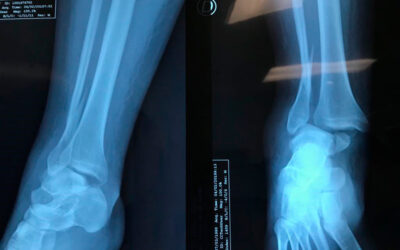

Osteotomía del cuello del primer metatarsiano y resección parcial de la cabeza

Osteotomía del cuello del primer metatarsiano y resección parcial de la cabeza para evitar sobre carga en la zona "mal perforante plantar" pie derecho.